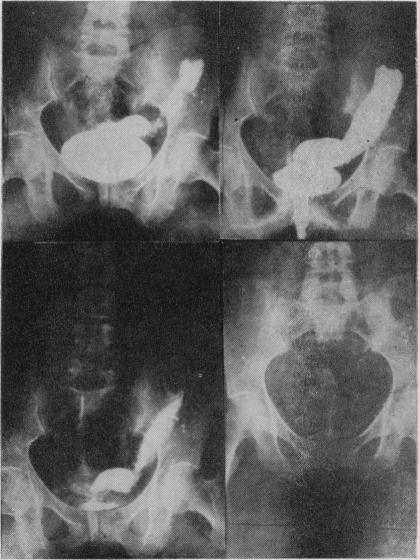

Sigmoid segment substitutes for bladder.